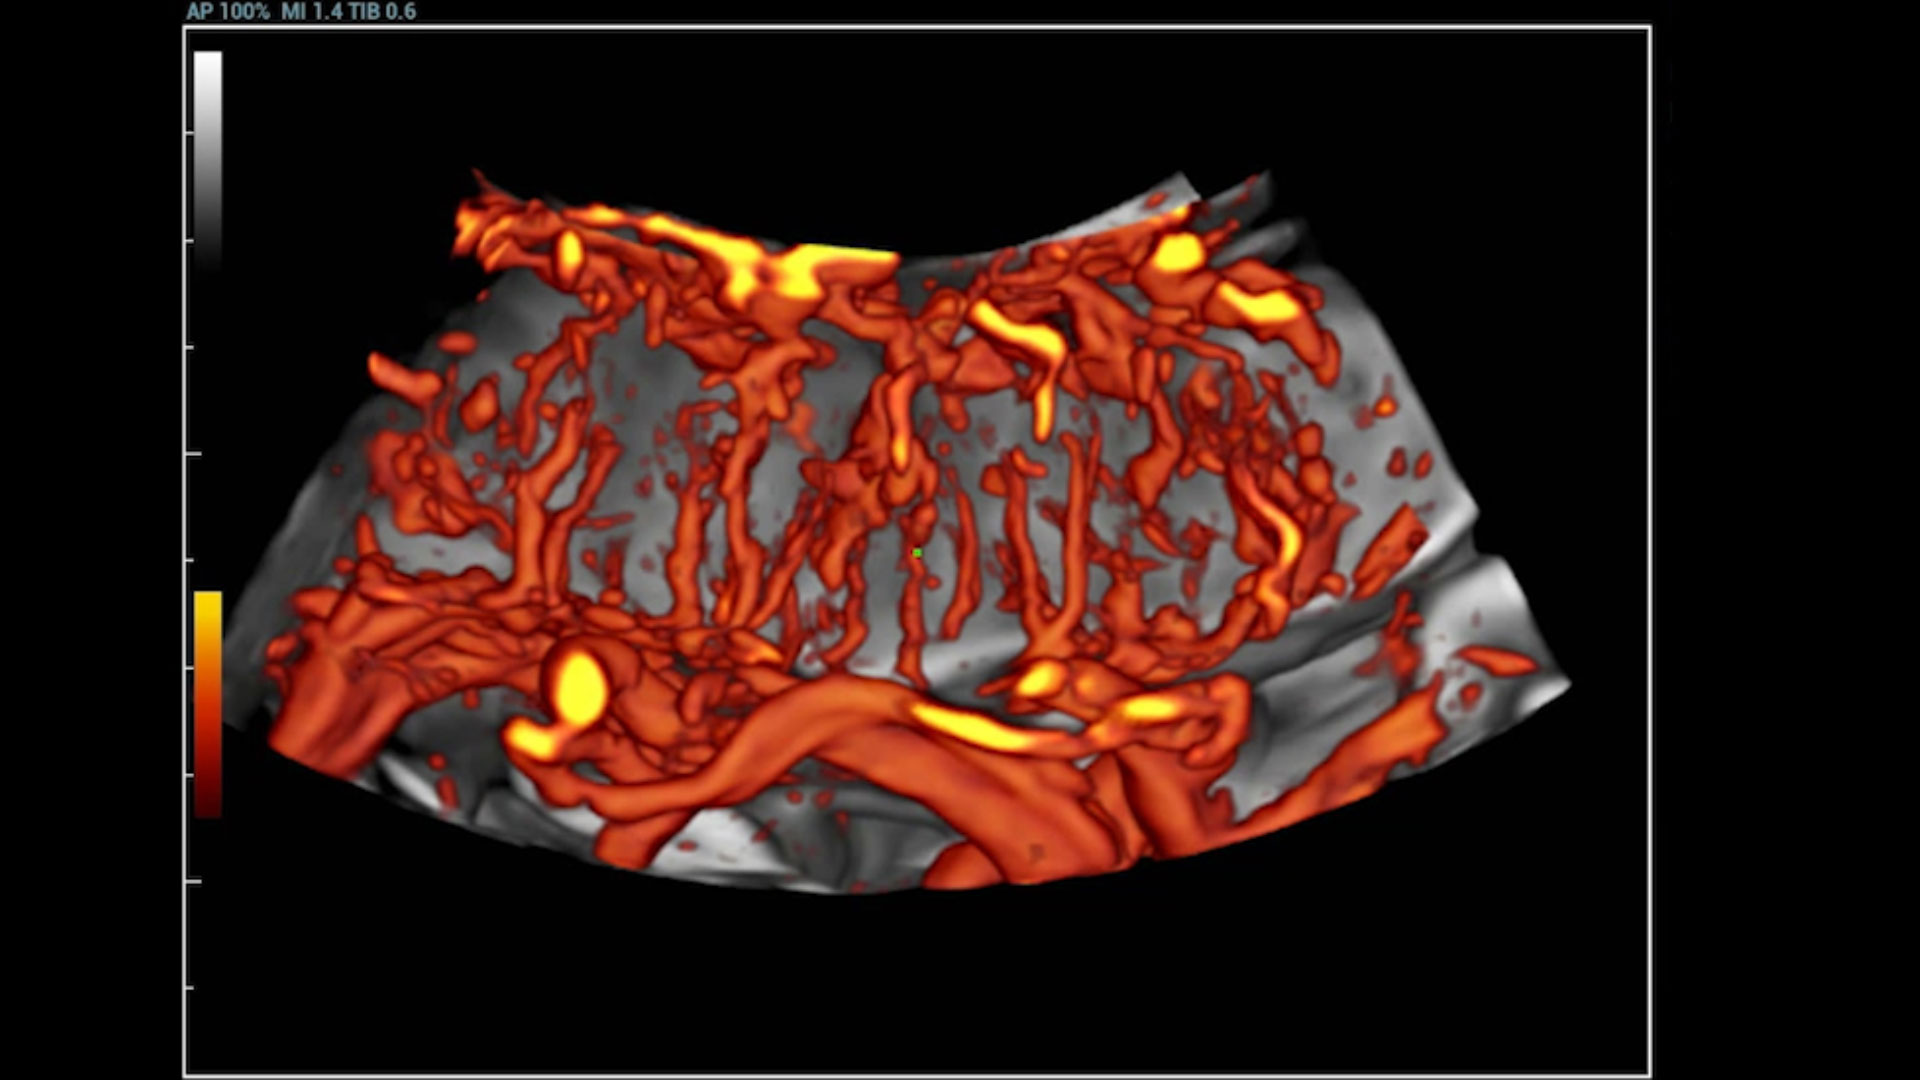

UMA (angiografia ultramicroscĆ³pica)

A tecnologia inovadora elimina as limita??es das tradicionais imagens com Doppler. Com resolu??o espacial e sensibilidade de fluxo ultra-altas, permite a detec??o de perfus?es de fluxos muito sutis e lentos, ampliando assim a aplica??o clĆnica da avalia??o qualitativa e quantitativa do ultrassom no cĆ©rebro fetal, rins, placentas, endomĆ©trios, ovĆ”rios etc.

UMA 3D ā Fluxo sanguĆneo perifolicular